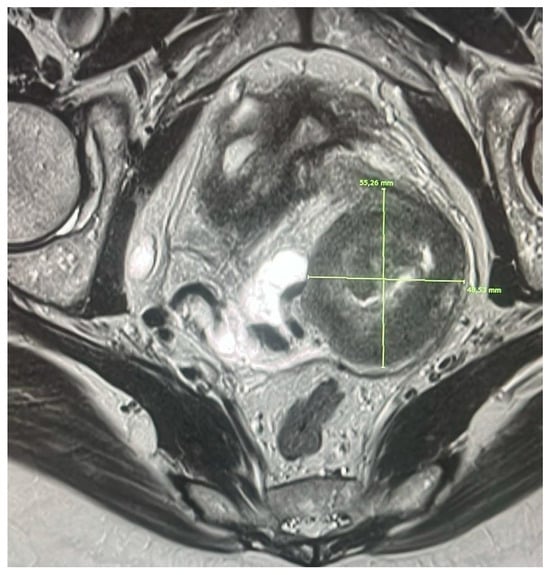

Stage IB3 according to the 2018 FIGO classification includes cervical tumors larger than 4 cm but confined to the cervix, thus without visible extracervical extension. This subgroup, defined as “bulky tumor”, is particularly clinically relevant due to its worse prognosis compared to stages IB1 and IB2 and because it significantly impacts therapeutic strategy.

In this context, magnetic resonance imaging (MRI) remains the imaging method of choice for accurate tumor volumetric assessment, surpassing both bimanual clinical assessment and ultrasound, thanks to its excellent soft-tissue resolution and the ability to obtain precise measurements in three orthogonal planes.

T2-weighted sequences are considered the most accurate method for three-dimensional tumor measurement, clearly surpassing clinical examination and transvaginal ultrasound. Bulky tumors appear as expansive masses with intermediate-to-high signal, replacing the normal cervical architecture. The lesion often appears heterogeneous, with central necrotic areas associated with greater biological aggressiveness [17].

T1-weighted sequences, however, generally show iso- or hypointense signal, but may reveal hyperintensity in cases of intratumoral hemorrhage or the presence of mucin, both common features of large lesions [18].

Diffusion-weighted imaging (DWI) sequences and ADC mapping are essential for assessing tumor cellularity. Bulky tumors show marked diffusion restriction, with significantly reduced ADC values, proportional to the high cellular density typical of these lesions [30,31]. The use of dynamic contrast-enhanced MRI (DCE-MRI) also allows analysis of the tumor’s vascular pattern: inhomogeneous or peripheral enhancement is often observed, with central avascular areas corresponding to necrotic zones [17].

Clinically, the presence of a bulky tumor is considered an unfavorable prognostic factor. Sizes > 4 cm are associated with an increased risk of lymph node metastases, local recurrence, and hematogenous dissemination. For this reason, in many centers, radical surgery is avoided in favor of combined treatment with concurrent chemoradiation (CRT), followed by high- or low-dose brachytherapy [19].

This approach has demonstrated greater efficacy in local disease control and functional preservation of pelvic organs. In this context, MRI is also crucial for the planning of adaptive brachytherapy (IGABT), allowing the precise delineation of target volumes (HR-CTV) and reducing the risk of underdosing, as demonstrated by prospective multicenter studies (EMBRACE-I) [17] (Figure 2).